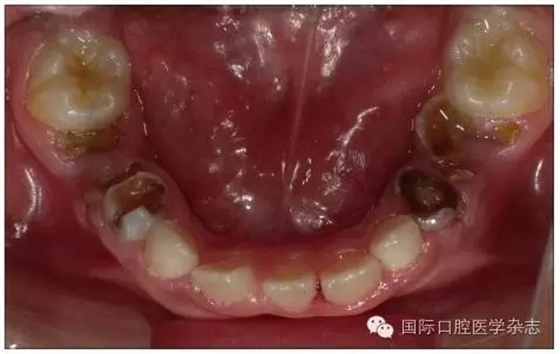

1.1.3 對牙弓長度的影響 乳牙齲病引起牙弓長度的變化并不只在乳牙因齲早失后,而是在乳牙發(fā)生鄰面齲之時即可發(fā)生。乳磨牙及乳尖牙鄰面的齲壞可引起牙冠近遠中徑縮窄,造成鄰牙向缺隙處移動、牙弓長度開始減小(圖1),這樣會引起日后恒牙列的擁擠與牙列不齊。在兒童口腔健康管理的理念指導下,應盡早治療乳牙齲病,特別是乳磨牙鄰面齲,盡量恢復患牙的外形和咀嚼功能,維持牙弓長度。對因齲壞牙而導致牙弓縮短的病例,可行間隙擴大矯治器(space regain appliance)以恢復牙弓長度,避免日后牙列擁擠的出現或減輕擁擠程度[2]。

圖1 下頜第一、第二乳磨牙重度齲壞,牙弓長度減少

Fig 1 Severecaries of the first and second mandibular primary molar intraoral arch length lessened